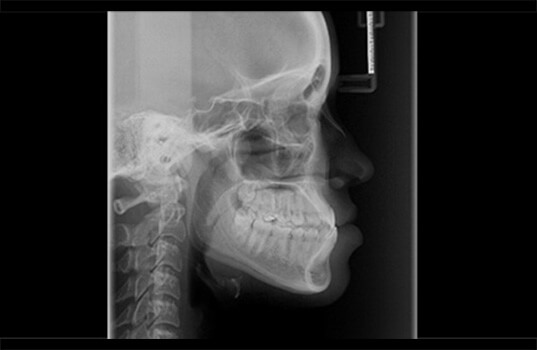

A Teleradiografia Lateral/Frontal é uma radiografia que serve para ver os ossos do crânio, mandíbula e pescoço. É usada na odontologia para descobrir problemas como fraturas, tumores, cistos, infecções, entre outros. Ela também é usada para planejar cirurgias na boca, avaliar o desenvolvimento de tratamentos como a colocação de implantes dentários e dar uma visão geral das estruturas ósseas e dentárias.

Também é comum que a Teleradiografia Lateral/Frontal seja combinada com outros exames radiográficos, como a panorâmica, por exemplo, para obter uma visão mais completa das estruturas ósseas e dentárias.